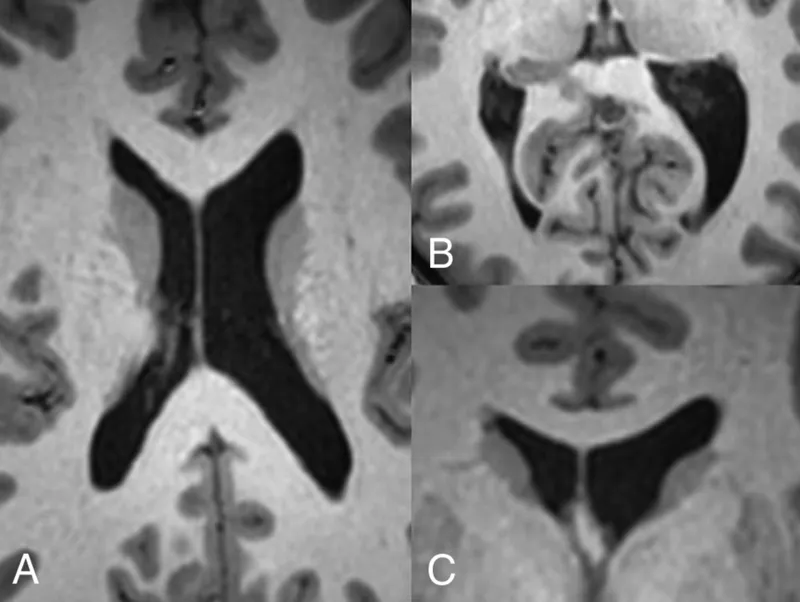

- Ventriculomegaly: Most consistent finding.

- ↑ in lateral and third ventricle volume.

- Represents a loss of surrounding brain parenchyma.

⭐ Enlargement of the cerebral ventricles is the most reliable and replicated structural neuroimaging finding in schizophrenia. This is due to a loss of brain tissue volume, not an overproduction of CSF.

- The most consistent and replicated finding is enlargement of the lateral and third ventricles.